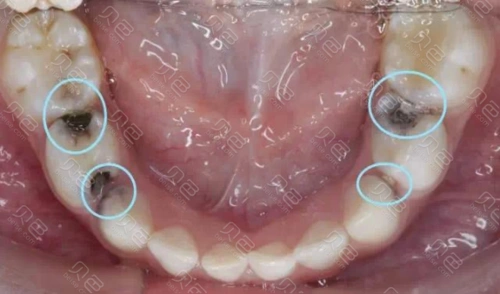

邻面龋很容易导致牙齿嵌塞,残留的食物在细菌的作用下会释放更多有害

日积月累,肆无忌惮的细菌,真能在你的牙缝里开个洞,也就是「邻面龋」